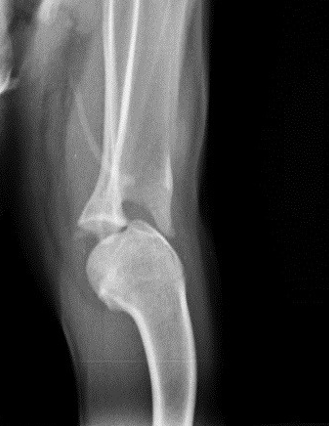

Die Röntgenuntersuchung beim Fachtierarzt für Chirurgie in Weiterstadt ergab, dass bei Ariel eine angeborene Missbildung vorliegt. Der rechte Oberarmknochen hat eine L-Form und zeigt nach hinten. Auch sind die Gelenkflächen nicht normal ausgebildet. Das führt dazu, dass Ariel die rechte Schulter nicht strecken und dadurch nur ganz gebückt laufen kann. Durch diese permanente Fehlhaltung ist leider auch das linke Schultergelenk luxiert (der Oberam luxiert nach außen und vorne). Ariel hat eine ganz schiefe Rückenlinie und die Prognose wäre nicht gut, wenn man nichts tut.....

Ihr linkes luxiertes Schultergelenk vor und nach der OP: